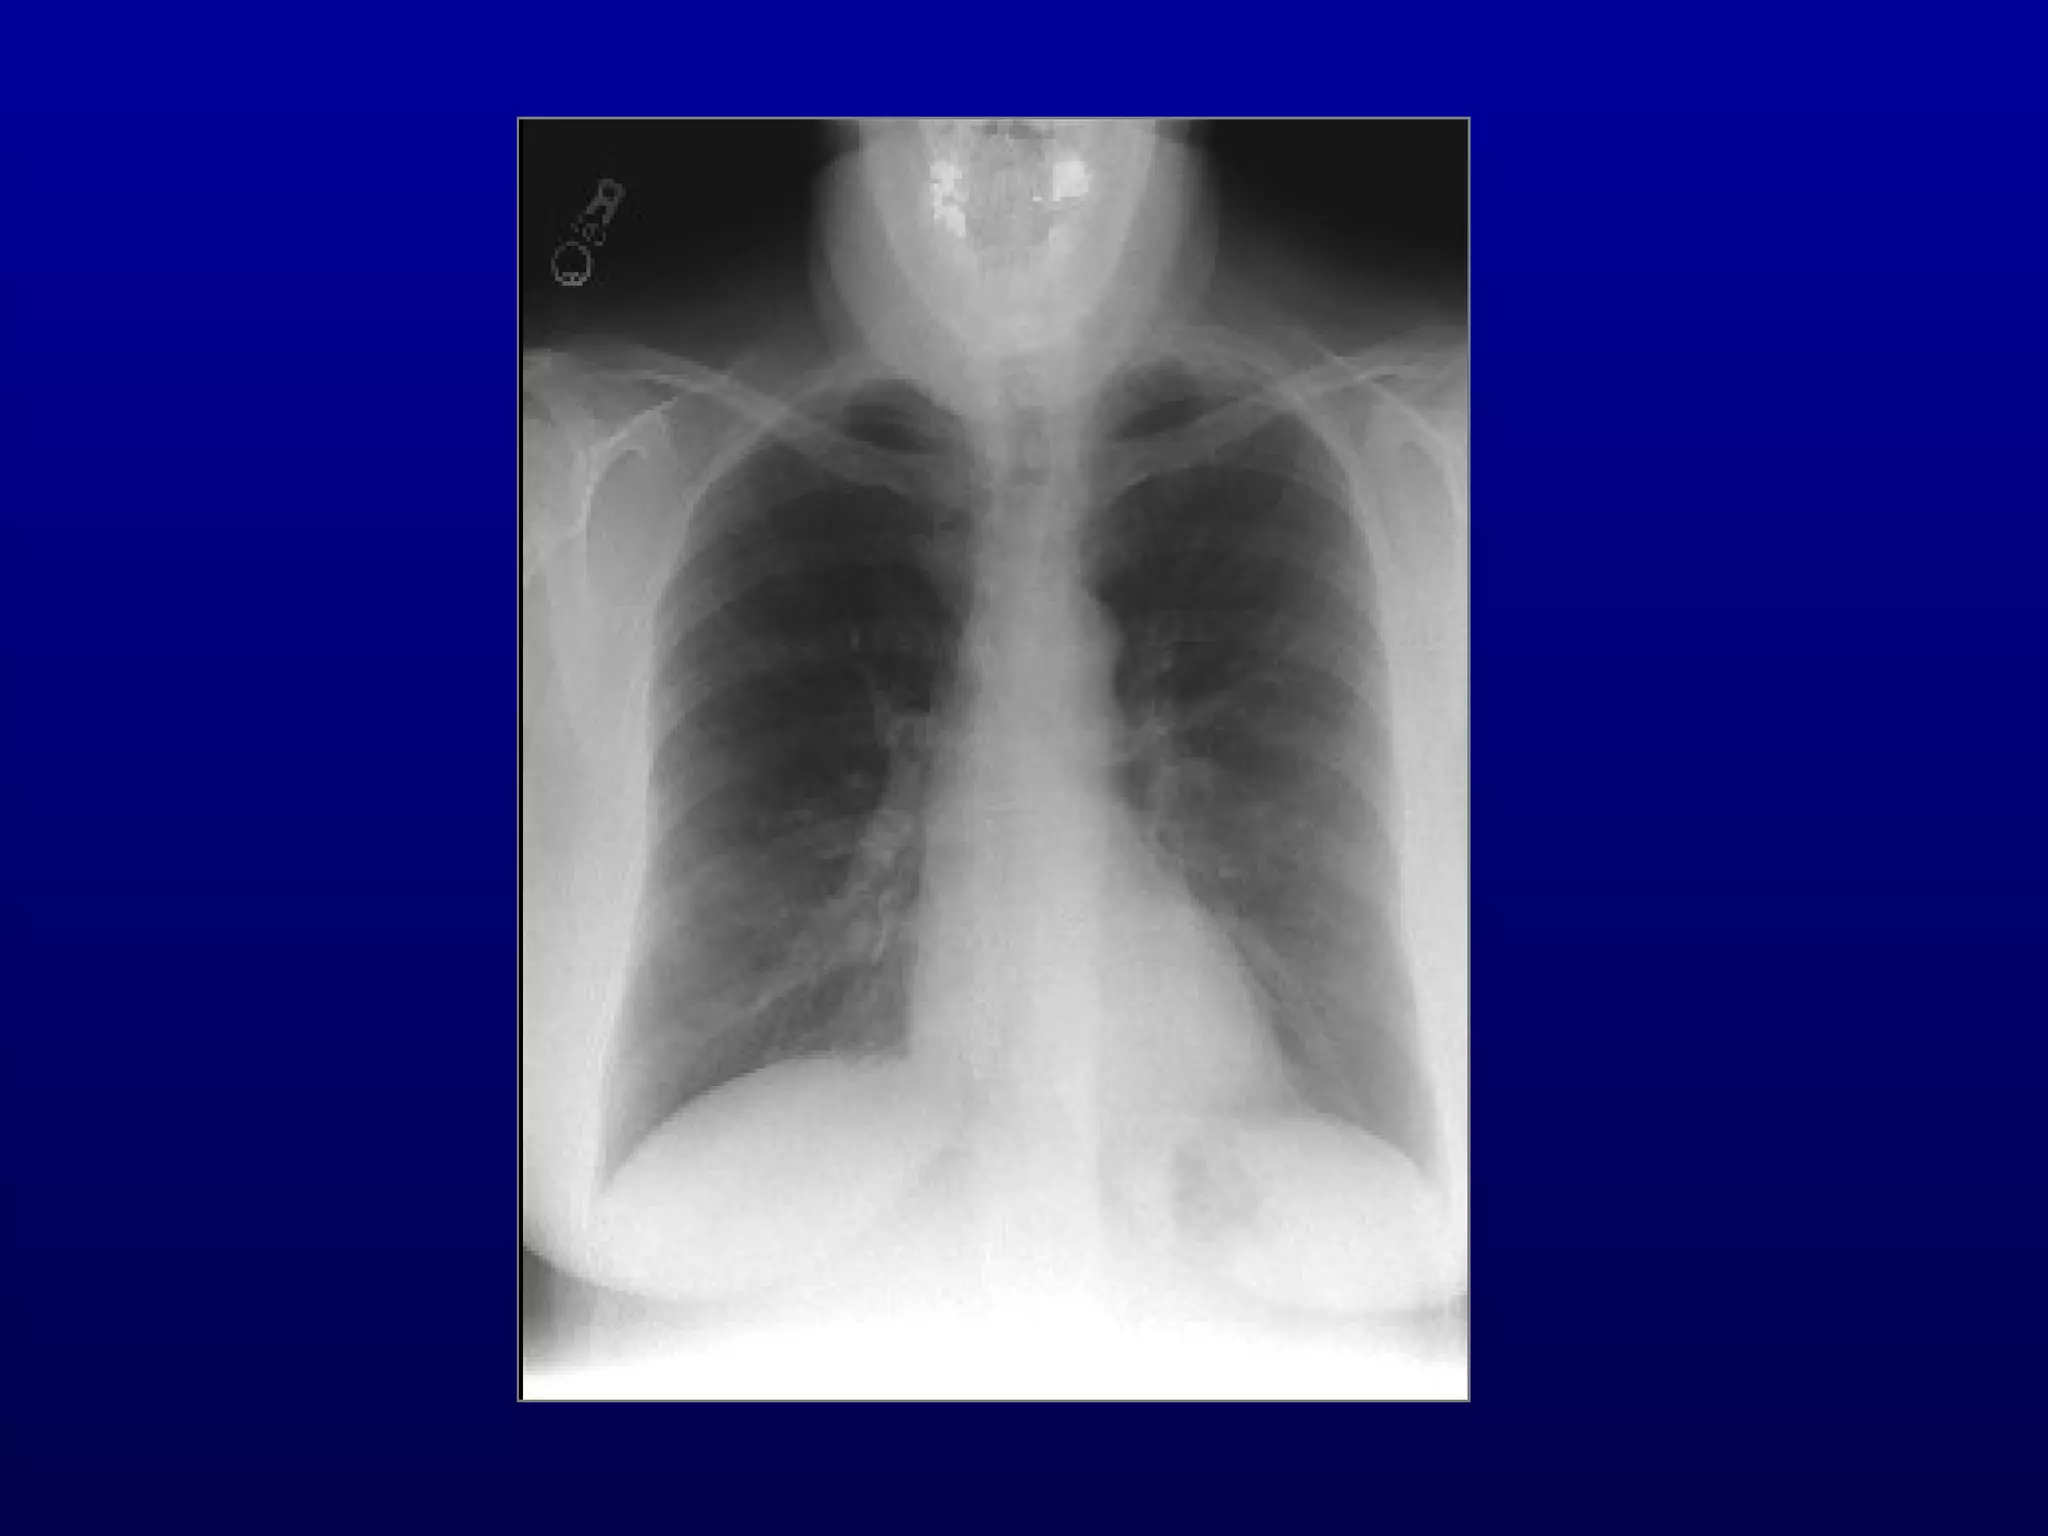

Case #2

• 64 y/o man referred for

Suggests restrictive process

Restrictive process